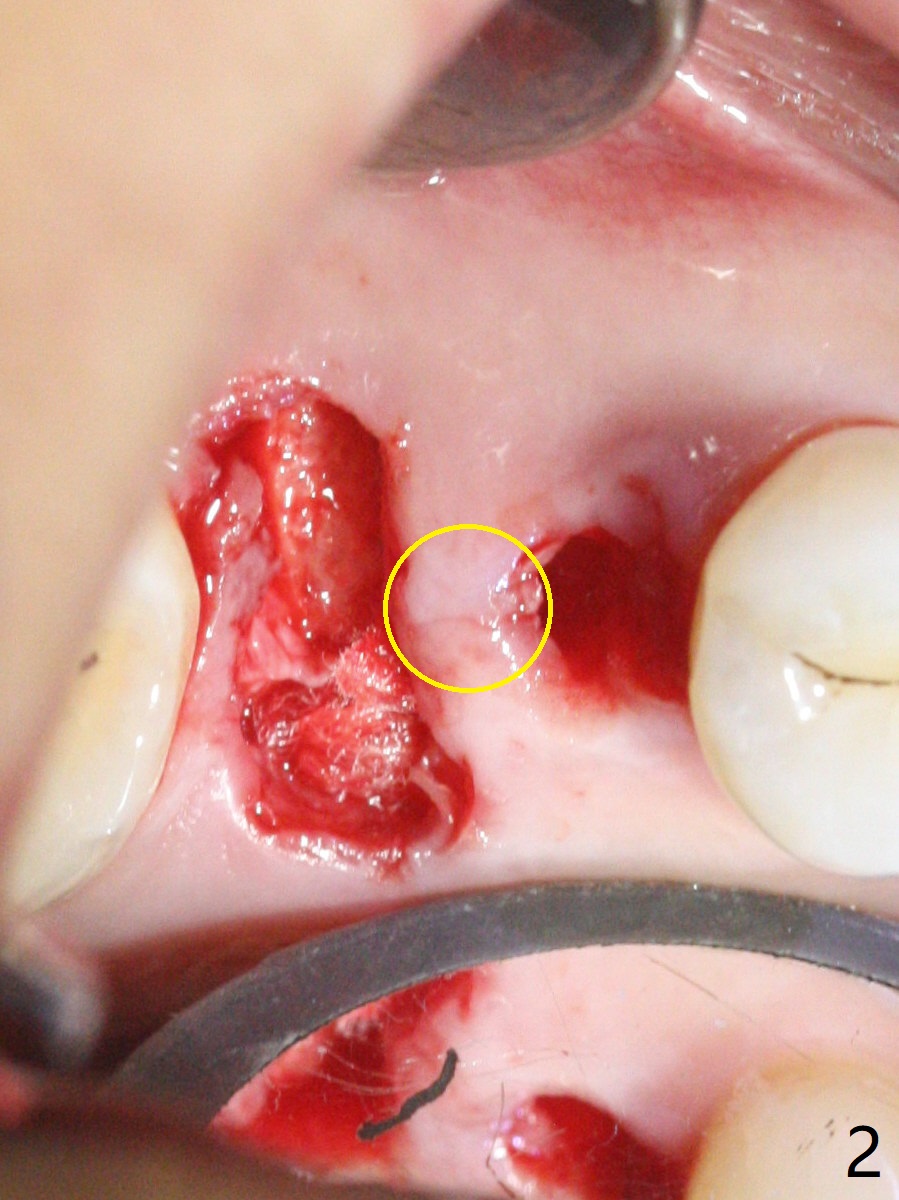

When the residual roots of the tooth #3 are removed, there is a gingival band over the septum (Fig.1 S). Osteotomy (Fig.2 yellow circle) would tear it off. To save the soft tissue, the buccal attachment is severed (Fig.3 black line), the flap is rotated palatal (Fig.3 curved arrow) and sutured in place (Fig.5 S). After sinus floor breakdown (use of sinus drill for 16 mm) and use of membrane lifter/water, two pieces of PRF membrane are inserted. The membrane is so slippery that it is easy to enter the sinus for further sinus membrane lift and later allograft placement (Fig.4 *). A 4.5x10 mm dummy implant is placed with high torque after 4x7.3 mm drill with 3 mm stopper so that 4.5x7.3 mm drill with 1 mm stopper is used before placement of a 5x8.5 mm final implant with ~ 35 Ncm (Fig.5-7). The patient reports anterior sinus wall tenderness with right nasal discharge a few days postop. The provisional has mobility without tenderness 1 week postop. It appears that the sinus membrane has been involved, which is quickly repaired probably by PRF. There is no pain when a 5.2x4(2) mm cemented abutment is torqued at 30-35 Ncm before impression (Fig.8). The surrounding soft tissue is healthy. When the permanent crown is delivered, the patient feels light pain when she bites hard. The discomfort persists 4 months post cementation (Fig.9). The crown/abutment is replaced with a healing abutment (Fig.10). There is no bone loss 4 months post healing abutment placement (14 months post implant placement, Fig.11). Upper Molar Immediate Implant, Prevent Molar Periimplantitis (Protocols, Table), Trajectory II, 31 Flap Not Transferred Xin Wei, DDS, PhD, MS 1st edition 07/26/2019, last revision 10/05/2020